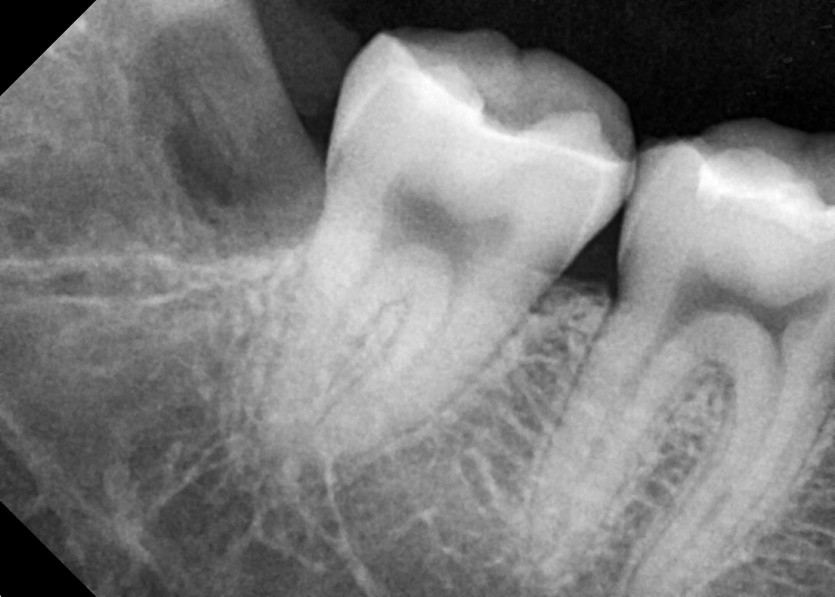

#38,48 사랑니 발치

구강 외과 전문의가 당일 발치했습니다.